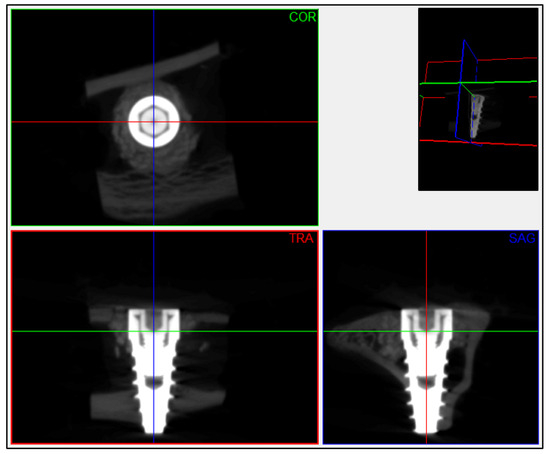

2.4. Micro-CT Imaging Study